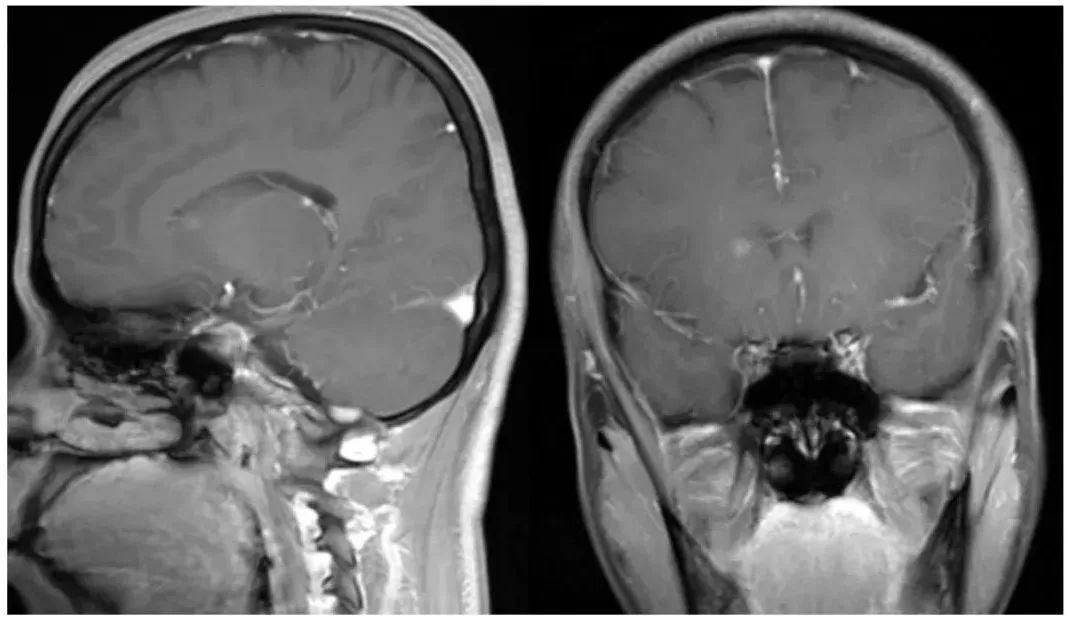

右侧尾状核头毛细血管扩张症,平扫看不到,增强呈结节样强化,无水肿,矢状位和冠状位仔细观察结节内可见静脉向室管膜下引流

右侧海马旁回毛细血管扩张症,平扫显示不清,增强呈毛刷状,可见引流静脉